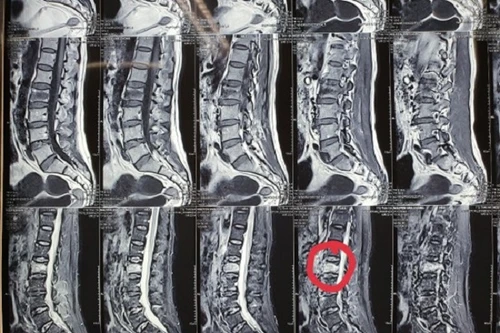

Suýt liệt cả hai chân vì đau lưng hơn 2 năm nhưng chủ quan không chịu đến bệnh viện